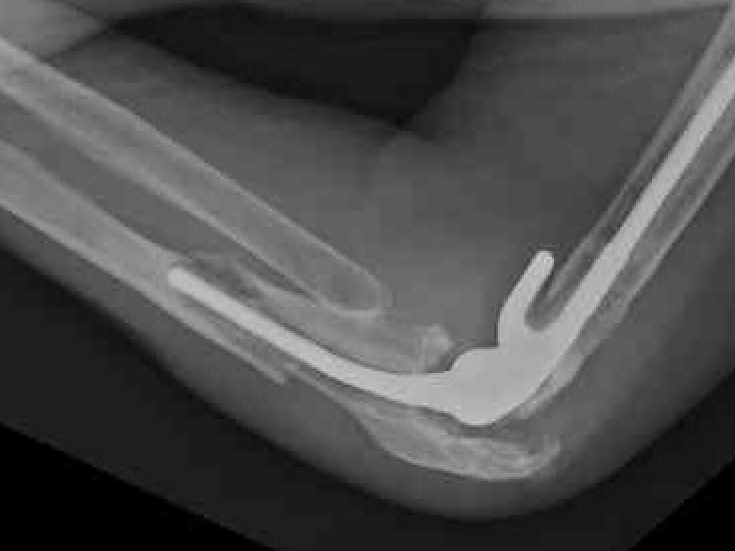

Aseptic Loosening

- systematic review of 3000 TEA

- loosening rates 10% for unlinked and 14% for linked prosthesis

Results

- revision with allograft - prosthesis composite

- 25 patients

- one nonunion / one malunion

- 84% TEA survival

Ulna allograft - prosthetic revision TEA